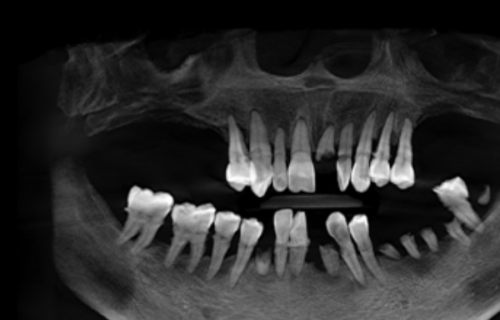

赵女士今年七十多岁,牙齿寥寥无几,残留牙齿情况特别差,无法承担正常的咬合功能。徐九波医生结合CBCT影像资料为她制定了全口种植手术方案。先为她种的下半口牙齿,手术做了将近两个小时。赵女士下半口种完后只吃了一点东西、休息了一会儿就修复了精神,没有出现身体不适。半个月后,赵女士接受上半口种植手术,术后仍未出现任何不适。半个月后,她还带着自己的姐妹来到鼎植口腔,希望徐九波医生为她们种牙。